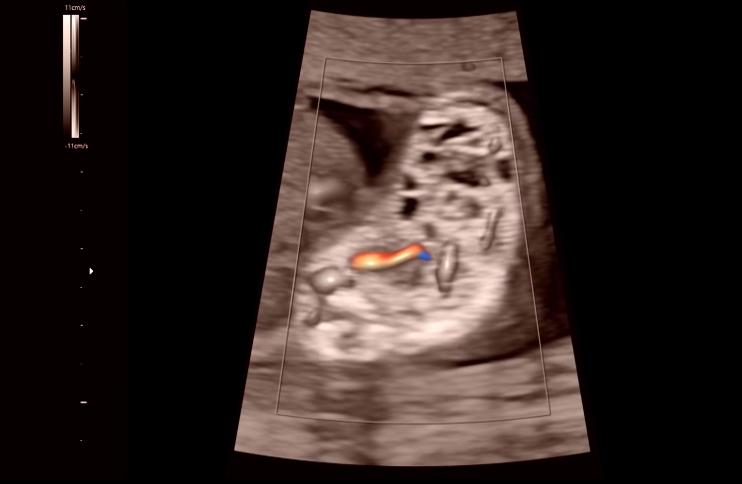

巴斯基医生决定采用间质内激光治疗,也就是把一根非常细的针从贝基的腹部穿刺进入胎儿的肺里,再把激光纤维插进细针中,通过发射高能的激光脉冲来堵住那根输送血液和营养物质的供血管

巴斯基医生只能依靠模糊的B超投影仪来寻找肿瘤的位置,尽管如此,他还是凭借丰富的经验将针管快狠准地扎进了准确位置,接着激光纤维的导入也很顺利,巴斯基医生没有丝毫犹豫,迅速找到了供血管的位置并利用激光堵住了它,不一会B超显示胎儿正在向胎盘泵血了,这就意味着手术结果的顺利和成功,巴斯基医生的沉稳操作甚至让肚子里的胎儿没有察觉到任何异常,听到这个天大的好消息,贝基和丈夫都喜极而泣,现在,她的女儿终于可以平安长大了。